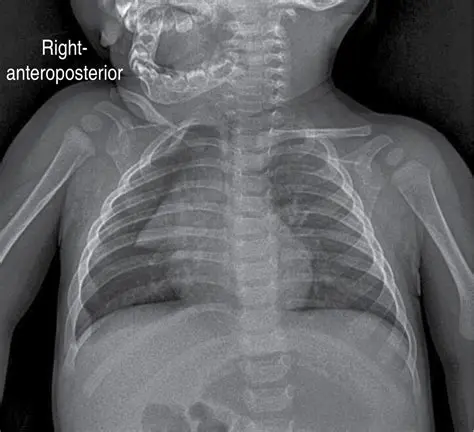

Key Features of the Pediatric Chest Atlas